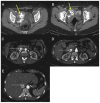

Uterine intravenous leiomyomatosis is an uncommon tumor, usually arising from the uterus, with nodular masses which extend intravascularly over variable distances and may reach the inferior vena cava, right atrium, and pulmonary arteries. Early diagnosis and surgical intervention are crucial as intracardiac leiomyomatosis not only causes cardiac symptoms but may result in pulmonary embolism and sudden death. Complete tumor resection is key in disease management, thus rendering cardiac-extending uterine intravenous leiomyomatosis one of the most challenging conditions for surgical treatment. The use of interventional radiology procedures can facilitate the surgical approach. We report the case of a massive pelvic recurrence of uterine leiomyomatosis with intracardiac extension and pulmonary embolism, analyzing management and surgical outcomes, highlighting the role of interventional radiology during the therapeutic pathway. Nonetheless, there are currently very few data available concerning the use of interventional radiology procedures in the therapeutic strategy of uterine intravenous leiomyomatosis with intracardiac extension.